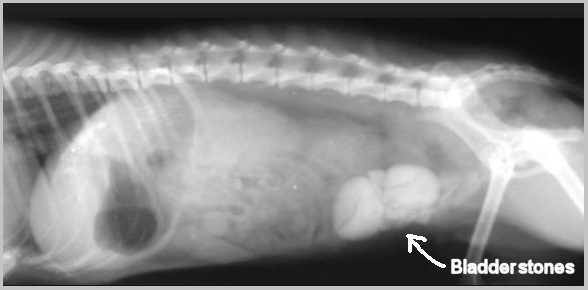

Hyperuricosuria is an inherited condition of the urinary system affecting several breeds of dog. The SLC2A9 gene codes for a protein that allows the kidneys to transport uric acid from the urine. Dogs with mutations in both copies of the SLC2A9 gene are predisposed to have elevated levels of uric acid in the urine, hence the name hyperuricosuria. Uric acid can form crystals and/or stones (uroliths) in the urinary tract. Dogs with hyperuricosuria most commonly present with symptoms of recurrent urinary tract inflammation, which include frequent urination, blood in the urine, and straining to urinate. They may also have loss of appetite, lethargy, weakness, vomiting and pain. Urinary stones in the bladder can cause urinary tract infections or more seriously, blockage of the Urethra. Both male and female dogs can be affected, but obstruction of urine flow is more common in males due to differences in anatomy. Although an x-ray can be used to exclude other types of stones, urate stones cannot typically be seen using x-rays and must be evaluated by ultrasound. Not all dogs with mutations in both copies of the SLC2A9 gene will have symptoms of disease, though they will have increased uric acid excretion in the urine.